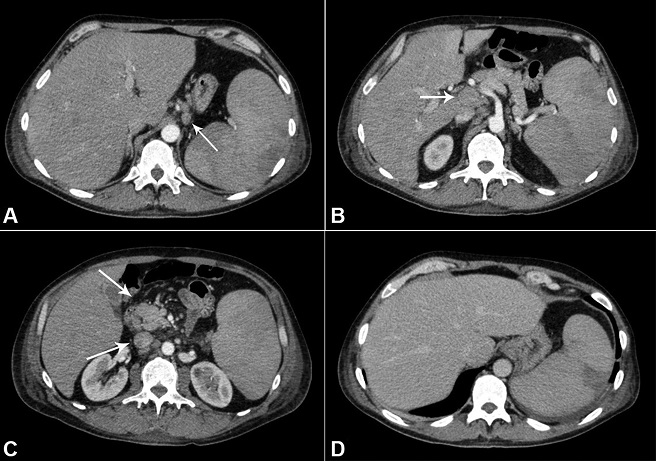

The computed tomography (CT) of the abdomen and thorax showed heterogeneous, enlarged, and confluent lymph nodes measuring 4.1 × 1.6 cm in the retroperitoneum (periaortic, interaortocaval, and portocaval), and in the perigastric, peri-esophageal, and pericardic regions. The spleen was enlarged and exhibited heterogeneous attenuation coefficient ( Figure 2). The axillary lymph nodes measured 1.5 × 1.3 cm